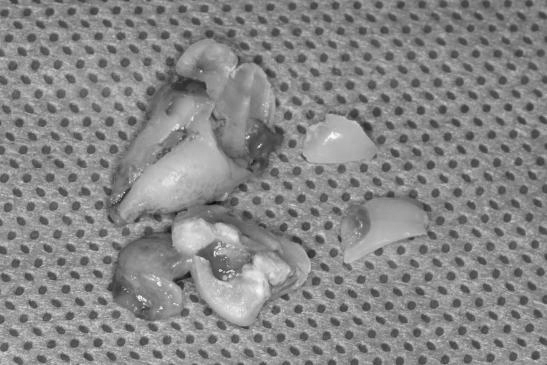

半小时后,崔小姐左侧的2颗智齿被完整拔除。“治疗中患者挺安静,也没说过疼,说明体验还是很不错的。”陈灵说。拔牙后,崔小姐恢复较好,无明显不良反应。

成功拔除智齿